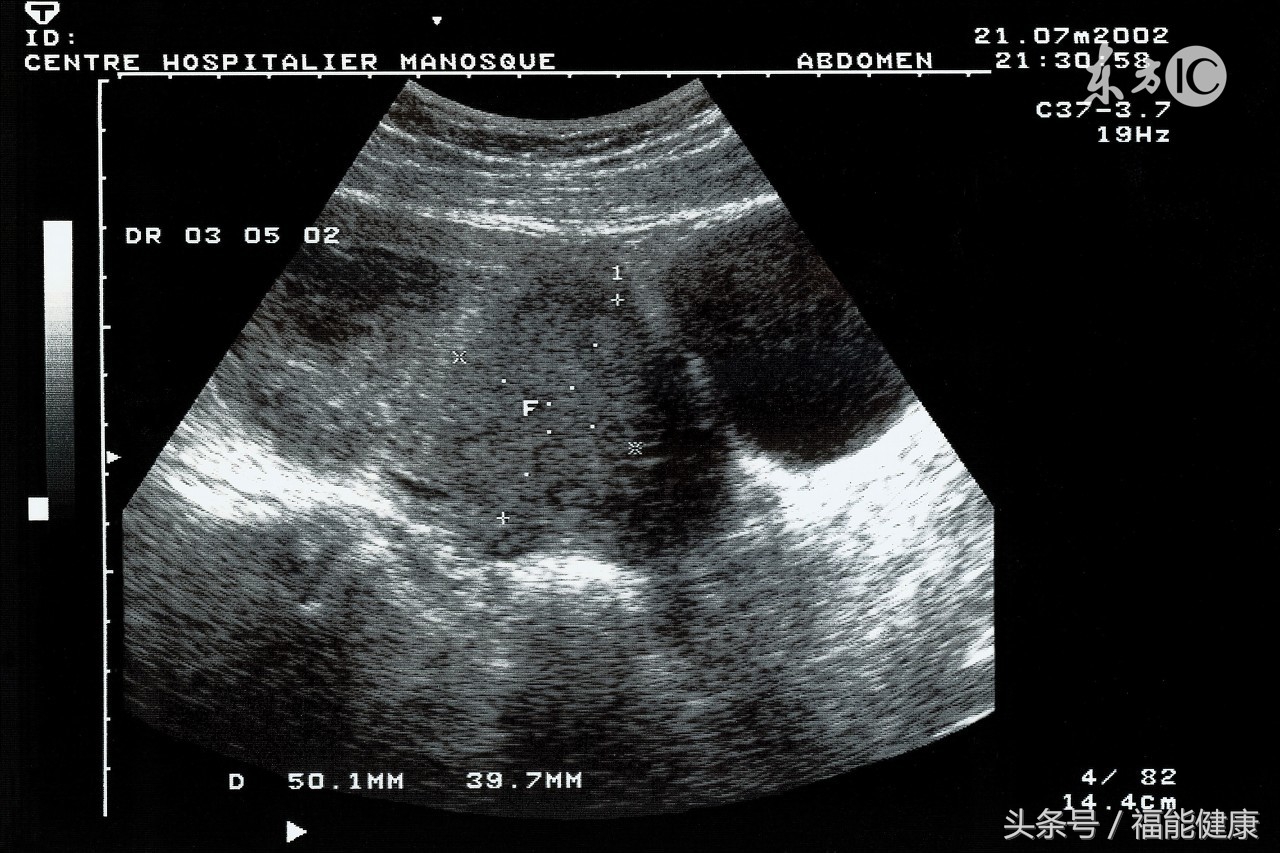

常规检查方法:彩超

目的:筛查卵巢癌

卵巢癌可发生在任何年龄,其死亡率居妇女生殖器官恶性肿瘤之首。但此疾病早期无任何症状,一般发现就是晚期。因此,女性应通过定期妇科体检的方式进行肿瘤筛查。

一年一次的卵巢彩超检查,是早期发现卵巢癌的惟一方法。对于有妇科肿瘤家族史的女性,应当积极就卵巢进行体检。

5、做子宫B超,膀胱里要积聚一定量的小便才能看得清楚;做妇科检查要排空小便。如果您既要做子宫B超又要做妇科检查,那您最好先做子宫B超,然后再做妇科检查。